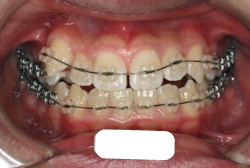

成長発育期の叢生症例・非抜歯治療

今回は「歯並びの凸凹を治したい」という主訴で来院したケースです。診断の結果、「成長発育期の叢生」と判明しました。叢生とは歯並びの凸凹のことですが、この方の場合は上顎が少々重症で、上の犬歯が外側へ飛び出し、いわゆる「八重歯」という状態でした。凸凹の解消のためには永久歯を抜歯して隙間を作って残った歯をきれいに配列する方法(抜歯法)と、歯列を拡大して配列する方法(非抜歯法)の2種類があります。歯列の拡大にはさらに2つの方法が有り、横方向へ拡大する場合と、臼歯を後方に移動させて拡大する方法があります。今回の症例のようなケースでは、横方向へ拡大してもあまり効果的ではなく、後方への移動が最適です。上の臼歯を後方へ移動させるために、今回はヘッドギヤという取り外し式の装置を、夜寝る時に半年ほど使用していただきました。

この方の場合、治療期間はヘッドギアを6ヶ月、マルチブラケット法を7ヶ月でした。治療後は凸凹が改善しただけでなく唇の審美性が大幅に改善しました。もちろん噛み合わせ的にも正しい状態が確立しています。